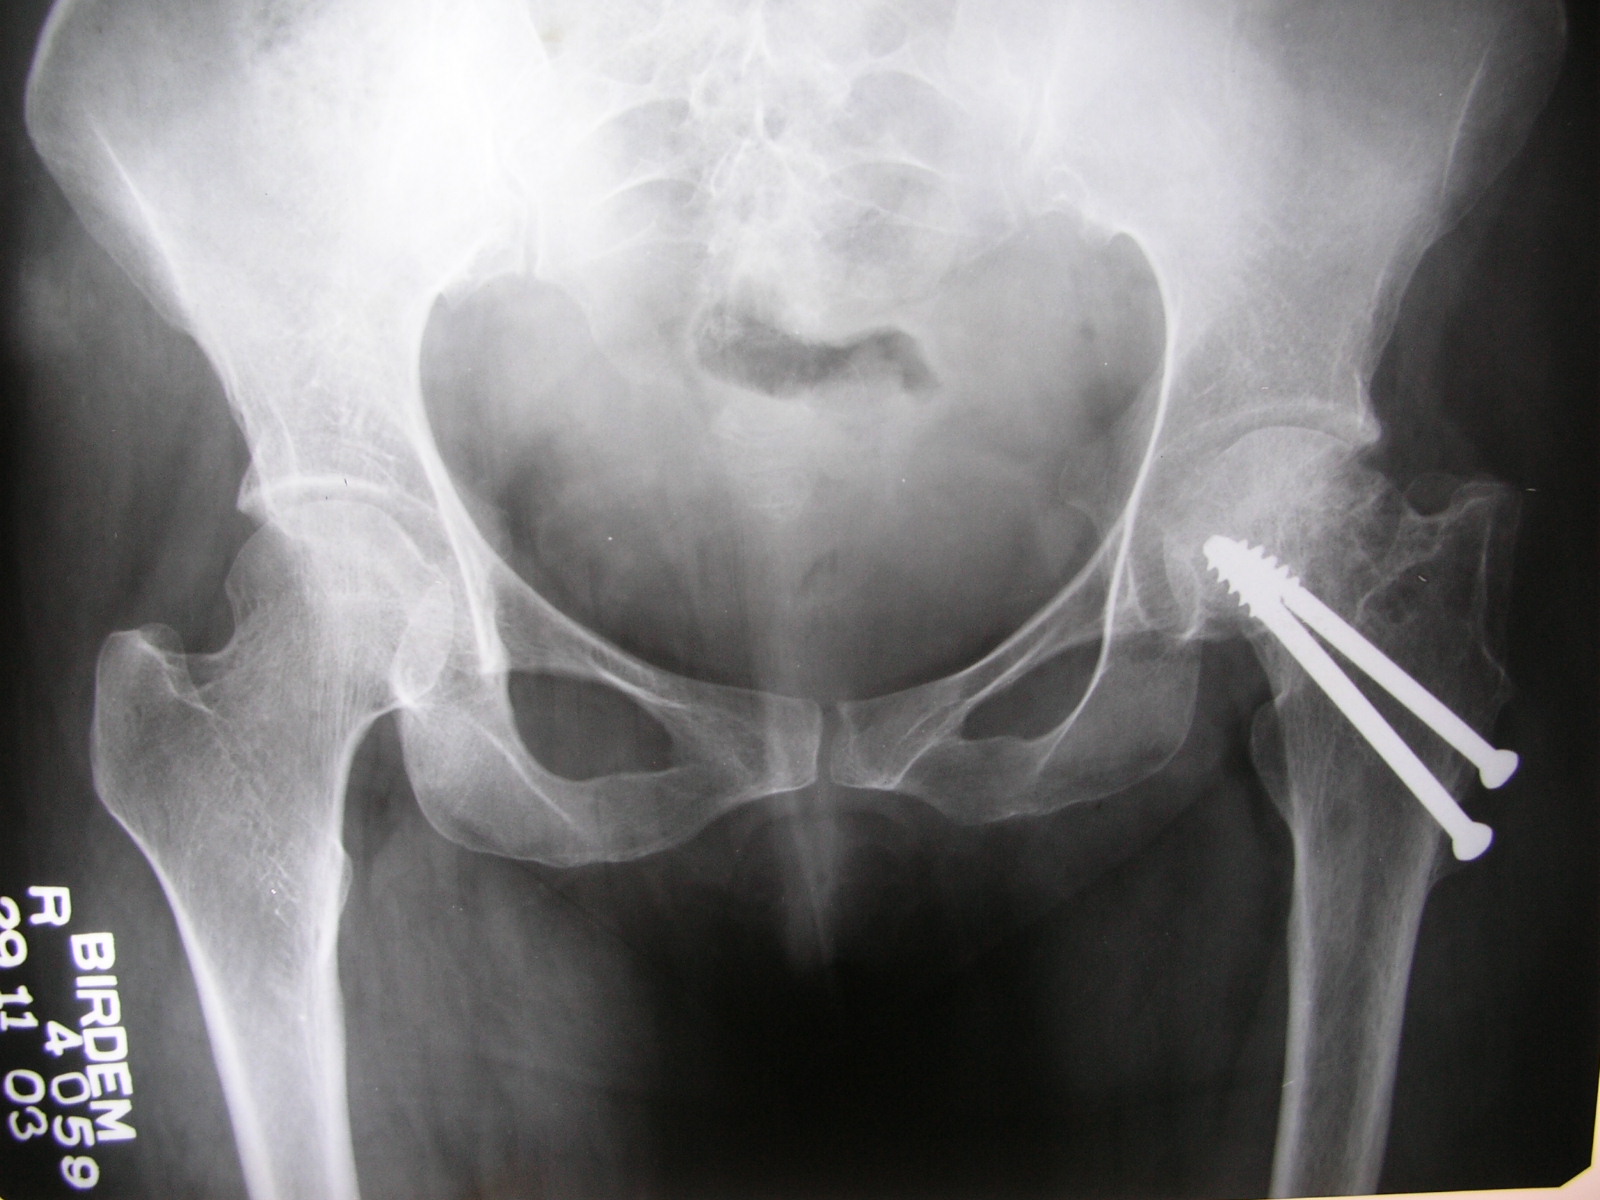

Femoral head fractures are associated with a posterior hip dislocation and acetabular fracture, although the fracture can occur in the absence of either of these conditions. It can sometimes happen after an acl reconstruction. Treatment consists of urgent closed reduction of the dislocated hip followed by nonsurgical or surgical management of any associated fractures.

And outcome of a hip dislocation. Femoral head fractures are rare traumatic injuries that are usually associated with hip dislocations. Treatment may be nonoperative or operative depending on the location of the fracture and degree of fracture displacement.

Background femoral head fractures:femoral head fractures: The standard of care for a displaced fracture where the blood supply is disrupted involves replacing the femoral head (hemiarthroplasty or a total hip. Metal screws are inserted into the bone to hold it together while the fracture heals.